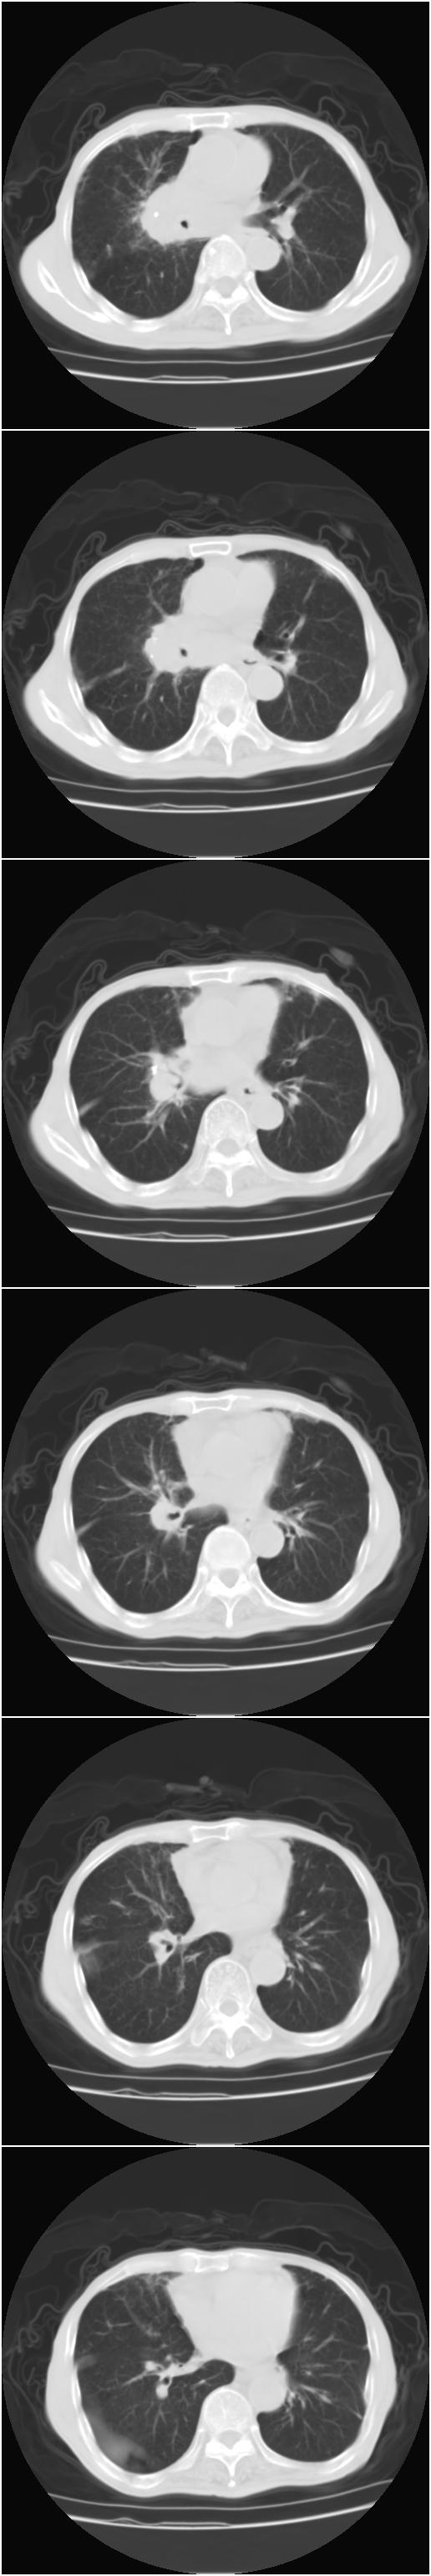

中心型肺癌 纵隔淋巴结转移

右侧中心型肺癌,右肺门,纵隔淋巴结转移。

右中心型肺癌 纵隔淋巴结转移

右侧中央型肺癌伴右肺门及纵隔淋巴结转移.

右侧中心型肺癌并纵隔淋巴结转移

1)考虑为:右侧中心型肺癌并右肺门及纵隔淋巴结转移。2)贲门癌术后改变。